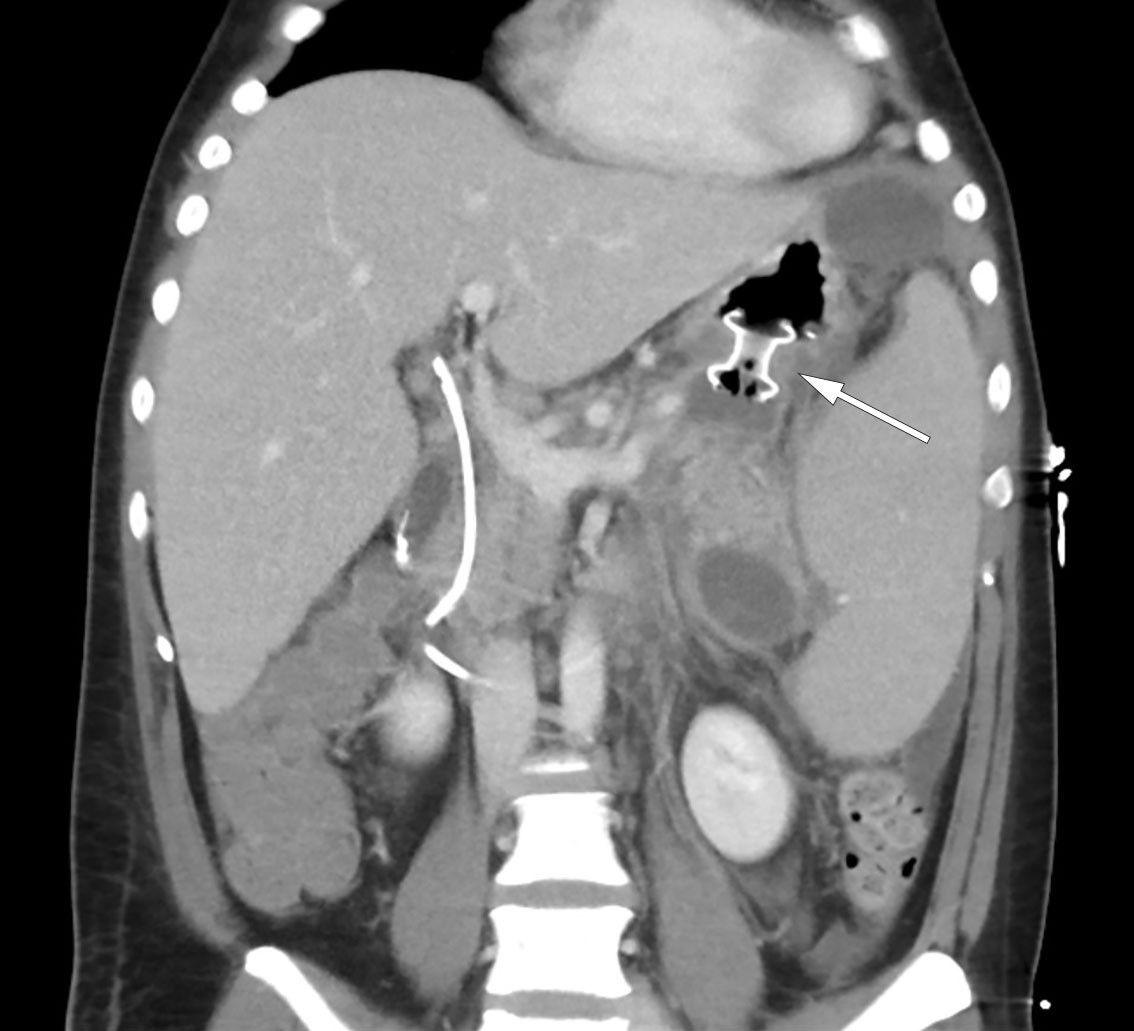

Den kliniske tilstanden ble i løpet av tredje døgn ytterligere forverret med sterke magesmerter. Pasienten ble overflyttet til intensivavdeling grunnet begynnende organsvikt med O2-behov. Pasienten var somnolent, men selvpustende, og i behov av 2–3 L O2 på nesekateter for å opprettholde adekvat oksygenmetning > 92 %. Videre forelå stigende INR-verdi på 1,9 samt fallende albuminverdi på 22 g/L (fra 45,6 g/L), som ga mistanke om blødningsforstyrrelse. I tillegg tilkom ny stigning i bilirubinnivå til 290 µmol/L, men i fravær av øvrig stigende nivå av lever- og galleprøver ble behov for ny ERC-undersøkelse avventet etter tverrfaglig diskusjon. Ytterligere diagnostikk med CT av abdomen og bekken viste nekrotiserende pankreatitt med peripankreatiske væskeansamlinger samt fri væske i buken (figur 2). Det var ingen tegn til intra- eller ekstrahepatisk kolestase. Videre forelå bilateral pleuravæske og sammenfalt lungevev, som kunne forklare pasientens respiratoriske forverring. I lys av forhøyet INR-verdi ble det avstått fra pleuratapping. I tillegg ble det bemerket forstørret milt (største lengde 21 cm).

Pasienten ble gradvis bedre og ble utskrevet etter 18 dager, men ble 3 dager senere reinnlagt på grunn av tiltakende smerter og tungpust. Kontroll-CT påviste avkapsling av peripankreatiske nekrotiske væskeansamlinger, med delvis avklemming av port- og miltvenen. Det var ingen kolestase, og lett avtakende fri væske i bukhulen. Blodprøver viste tegn til betennelse, og det ble startet peroral antibiotikabehandling i form av trimetoprim/sulfametoksazol 160 mg/800 mg, to ganger daglig, samt metronidazol 400 mg tre ganger daglig, på mistanke om sekundærinfiserte nekroser. Pasienten kunne åtte dager etter andre innleggelse utskrives til eget hjem uten videre antibiotikabehandling. Det ble påfølgende uke planlagt endoskopisk transgastrisk drenasje av innkapslede nekrotiske væskelommer, såkalt walled-off necrosis (WON), grunnet avklemming av port- og miltvenen.

Tre dager etter andre utskrivelse ble pasienten på ny innlagt med økende smerter i venstre del av abdomen, strålende til rygg. Blodprøver viste leukocytose med leukocyttall 28,1 × 109/L og CRP 7,6 mg/L. Det forelå lett redusert nivå av hemoglobin på 12,4 g/dL samt forhøyet nivå av bilirubin på 53 µmol/L. Lipasenivået var på 81 U/L og minimalt forhøyet. Natt til tredje dag etter reinnleggelse var pasienten normotensiv, men takykard med pulsfrekvens på 134 slag/min, respirasjonsfrekvens på 44 pust/min og oksygenmetning på 91 % på romluft. Han var blek og klam og smertepåvirket med overflatisk respirasjon. Gjentatt CT-diagnostikk viste økende ascites, men avtakende størrelse på største væskelokulament. Det var ingen gallegangsdilatasjon, men det var tilkommet basale lungefortetninger på venstre side samt små mengder pleuravæske. Sistnevnte er ikke uvanlig i lys av pankreas' lokalisasjon opp mot diafragma, hvor inflammasjonsforandringene kan være utbredte og affisere lungehulen. Biokjemisk forelå forhøyete inflammasjonsprøver, med leukocytter på 22,5 × 109/L og CRP på 51 mg/L samt fallende hemoglobin på 10,6 g/dL. Pasienten ble bestemt overflyttet til intensivavdeling for optimalisering av smertelindring med epiduralkateter samt henvist til fremskyndet drenasje av innkapslet nekrose.

Neste dag var pasienten febril med temperatur 38,5 °C, men uten behov for oksygen. Innkapslet nekrose ble behandlet med anleggelse av en lumen-apposing metal stent (LAMS) av typen Hot AXIOS, et system utviklet for endoskopisk ultralydveiledet drenasje av innkapslet nekrose via magesekken. Videre ble det plassert ernæringssonde i tynntarmen, og pasienten startet med næringstilskudd. Påfølgende dager opplevde pasienten et svingende forløp, både klinisk og biokjemisk. Det ble startet bredspektret, intravenøs antibiotikabehandling i form av meropenem 1 g tre ganger daglig grunnet stigende CRP på 148 mg/L. Videre falt hemoglobinnivået til 6,9 g/dL, og pasienten ble besluttet transfundert med tre poser erytrocyttkonsentrat. CT-kontroll viste derimot betydelig redusert størrelse av den innkapslede nekrosen etter anlagt stent, og kompresjon av kar hadde opphørt (figur 3). Pasienten fikk utført nekrosektomi ved gastroskopi, hvor det ble fjernet større mengder dødt vev. Over de kommende dagene ble pasienten gradvis mobilisert, med samtidig bedret respirasjon og god diurese støttet av slyngediuretika. Det forelå sterile blodkulturer i to sett, men oppvekst av Staphylococcus epidermidis i urin av usikker klinisk betydning. Epiduralkateter ble seponert, opioider kunne nedtrappes i takt med økt mobilisering, og pasienten ble overflyttet til gastrokirurgisk sengepost dag 10 etter tredje reinnleggelse.